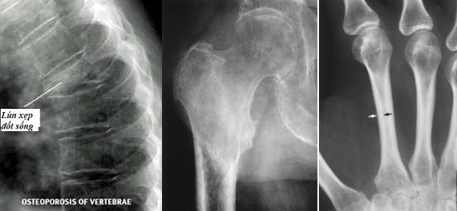

Gãy xương: Các vị trí thường gặp là gãy đầu dưới xương quay, gãy cổ xương đùi, gãy các đốt sống (lưng và thắt lưng); xuất hiện sau chấn thương rất nhẹ, thậm chí không rõ chấn thương.

Biến dạng cột sống: Gù, vẹo cột sống, giảm chiều cao do thân các đốt sống bị gãy.

Hình ảnh đốt sống tăng thấu quang, biến dạng thân đốt sống, với các xương dài thường giảm độ dày vỏ xương.